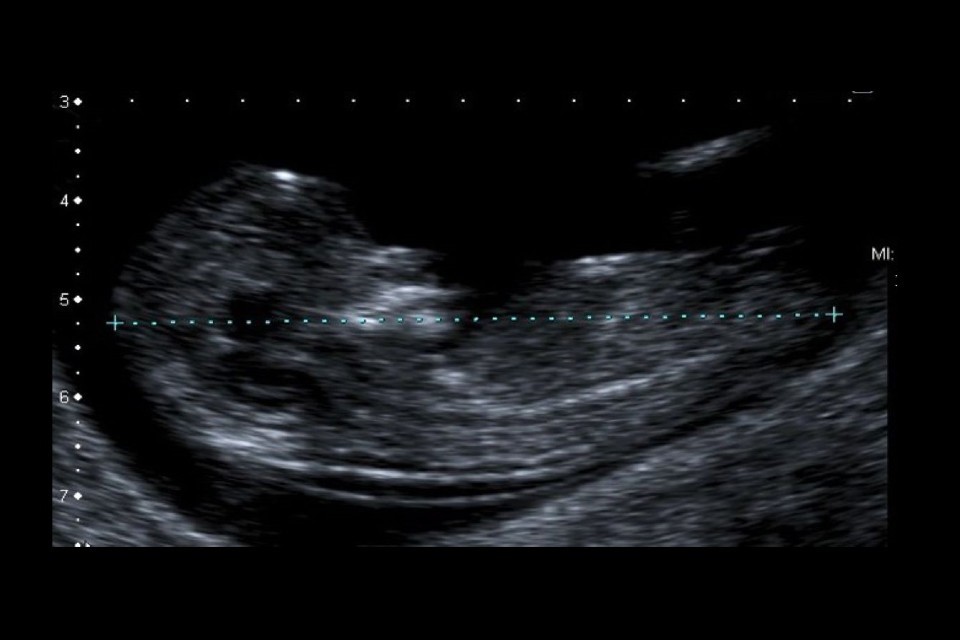

Example 1 shows 2 ultrasound images of a CRL and an NT that meet all the criteria. There is also a screenshot of what the accompanying image review tool would look like for both images.

Example 1